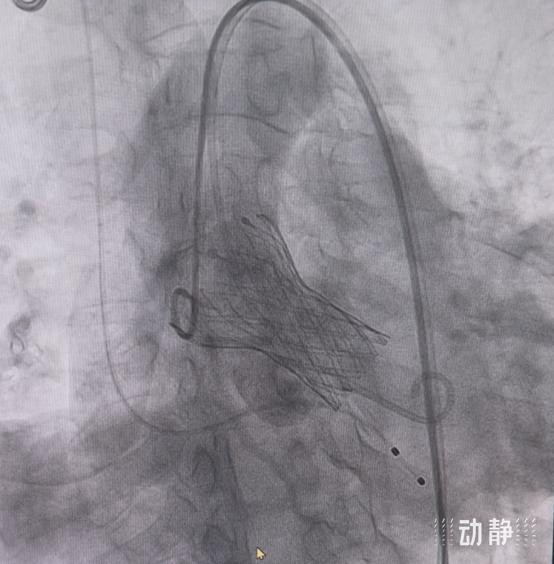

术中,手术团队通过股动脉入路,将人工心脏瓣膜精准输送至病变位置,成功解除主动脉瓣狭窄。术后造影显示,人工瓣膜位置形态良好,压差从术前98mmHg降至3mmHg,血流动力学显著改善,患者恢复良好。